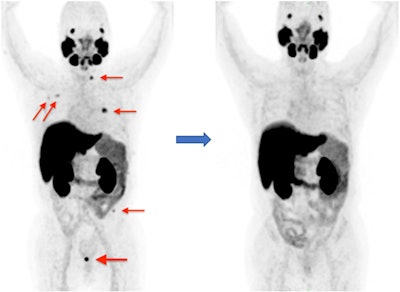

PET/CT imaging with an experimental F-18 prostate-specific membrane antigen (PSMA) radiotracer improves the care of patients with recurrent prostate cancer, according to a study published on January 7 in Research in Diagnostic and Interventional Imaging.

Researchers at the First Affiliated Hospital of Wenzhou Medical University in China showed that treatment decisions were improved in more than half of the patients who underwent PET/CT imaging using F-18 PSMA-1007.

The study showed that the stage of the disease changed in 63.2% of patients. Of these patients, 93.1% were upstaged. Results on F-18 PSMA-1007 PET/CT scans also prompted additional imaging in 57.1% of patients. Ultimately, the treatment category of 34.2% of patients changed from palliative to curative treatment, and 18.4% changed from curative to palliative treatment, for an overall treatment strategy change in 52.6% of patients, the authors wrote.